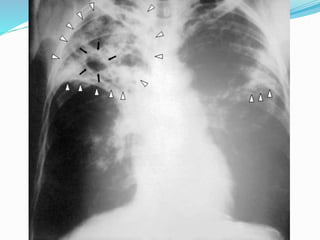

 Laki-laki, 65 th, sebelum OAT

 6 bulan pasca OAT

 Laki-laki, 65th, sebelum OAT

 6 bulanpasca OAT